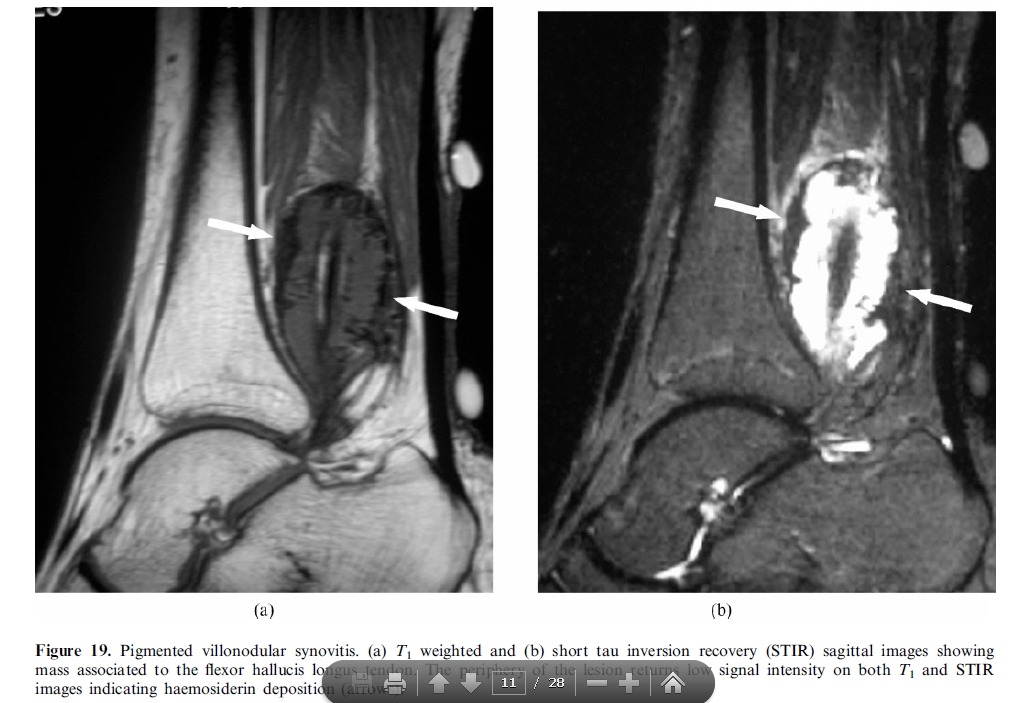

Imaging plays a major role in the management of ankle and foot problems. Most conditions are assessed by plain

films alone. MRI is an excellent technique for those cases where the diagnosis is uncertain as it can exclude most

clinically relevant pathologies. Ultrasound is an excellent tool for imaging focal soft tissue abnormalities. CT is

occasionally useful when bony detail is required. Bone scintigraphy has a limited role and has been largely replaced by MRI in many centres. The main reasons for referral are swelling and pain. Many conditions of the ankle and foot are related acute or repetitive trauma.